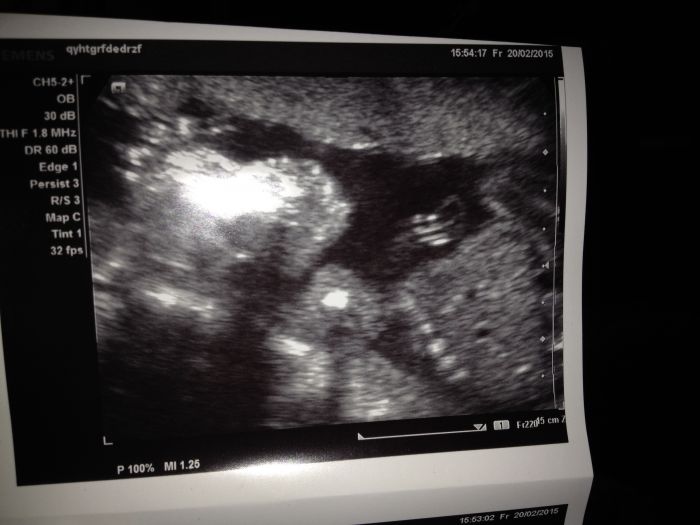

Ahojky holky,byla jsem tu naposledy pred měsícem, tak jsem se prisla mrknout co nového. Jinak ted jsem 21+5 tt a uz cítím docela dobre kopanecky:)krasnej pocit. Uz mame i pravidelný intervaly, tak se vždy těším na určitou hodinu a čekám :). Na velkém utz jsem uz take byla, akorat me trošičku postrasili, ze na miminko neco na srdicku(focus) a musím ted 14 dni čekat na výsledky a pak se uvidí:( nemáte s tím nějaká zkušenost? Nevim co od toho čekat...jsem docela vyplasena:(..dělohu mam take porad pod pupkem a to jsem 22 tt. Tak snad bude vse ok. Zavolám nějaké fotecky miminka:)

jé, krásná fotečka :)